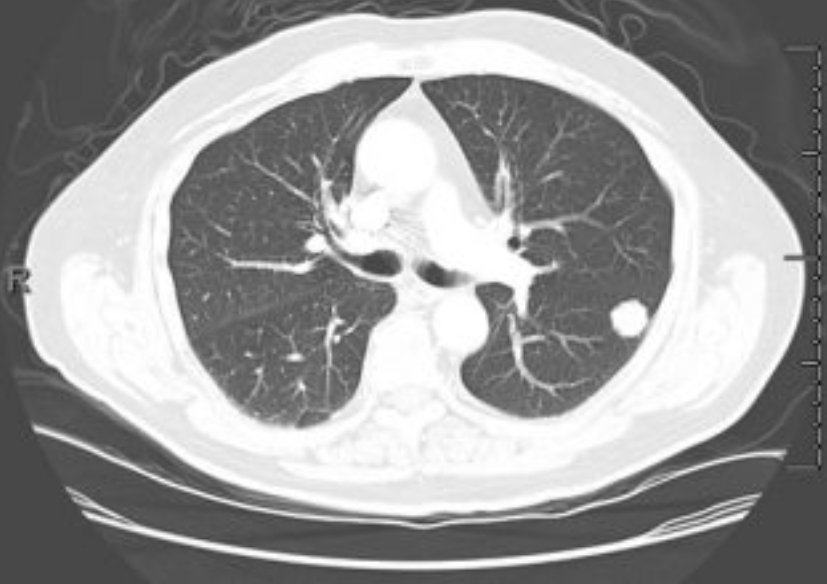

이 검사는 X선을 여러 각도에서 투사해 가슴 속을 단면으로 나누고, 컴퓨터가 이를 조합해 입체적으로 보여줍니다. 흉부ct로 볼수있는 질환 폐, 기관지, 심장, 혈관, 흉막, 림프절, 늑골까지 모두 관찰할 수 있어요. 몸을 절개하지 않고 내부를 볼 수 있으니 환자에게 부담이 적습니다. 조영제(혈관이나 염증 부위를 선명하게 보여주는 약물)를 사용하는 경우에는 정맥으로 주입하기도 하지만, 대부분은 통증이 거의 없습니다.

흉부CT는 이야기가 달라요. 얇게 자른 단면을 수백 장 촬영하기 때문에, 작은 병변도 놓치지 않습니다. 마치 산 전체를 한 장의 사진으로 보는 엑스레이와 달리, CT는 나무 한 그루 한 그루를 자세히 보는 느낌이에요. 예전에 병원에서 일했던 친구 말로는, 엑스레이에 아무 이상이 없던 환자가 CT에서 폐암 초기 진단을 받은 경우도 많았다고 합니다. 그만큼 CT는 정밀한 탐색 도구입니다.

흉부ct로 볼수있는 질환 폐질환뿐 아니라 심장과 혈관, 흉막, 림프절, 뼈 구조까지 한 번에 보여줍니다. 폐렴, 결핵, 폐기종, 기관지확장증, 간질성 폐질환 같은 호흡기 질환은 기본이고, 폐에 생긴 작은 결절이나 혹도 세밀하게 확인할 수 있습니다. 폐암이나 전이암처럼 초기에 증상이 거의 없는 병은 CT로 발견되는 경우가 많아요.

흉부CT는 병이 있는지 없는지를 넘어서, 병의 진행 정도와 주변 장기 침범 여부까지 보여줍니다. 예를 들어 폐암의 경우, 5mm 미만의 아주 작은 결절까지 찾아내고, 종양이 혈관이나 기관지에 닿았는지도 확인합니다. 초기에 잡아내면 완치율이 크게 높아지죠.